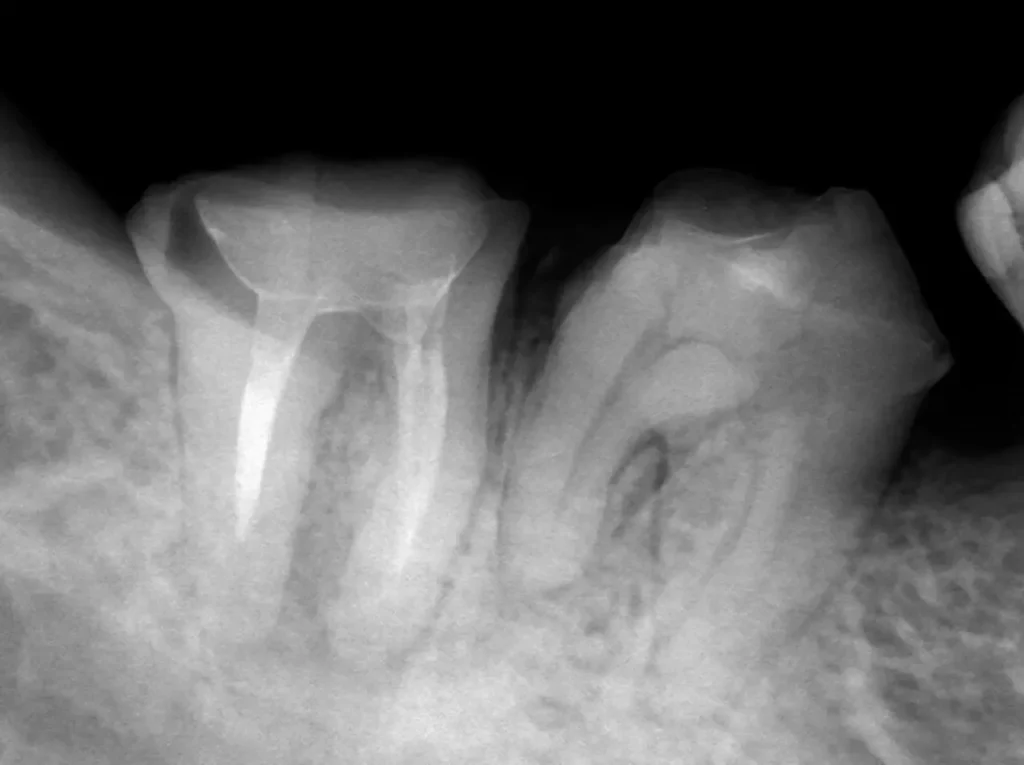

自費根管治療症例3 治療前

紹介元で半年間根の治療を受けているがうずく痛みがとれないので紹介されて受診

初診時

根の先が黒ずんで炎症があります

術中

症状も消え根の先まで清掃できました

術後

理想的に終了し土台も作製、被せ物は依頼元で行うことになりました